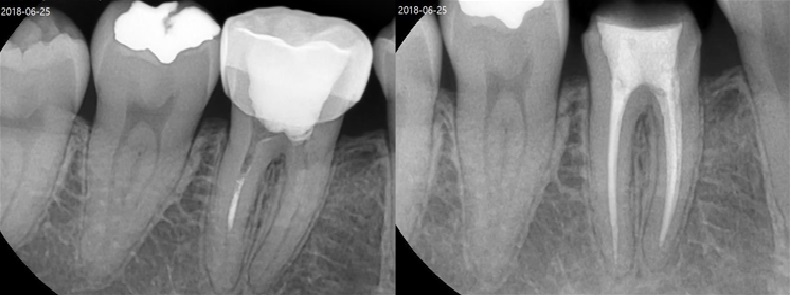

치료전후사진